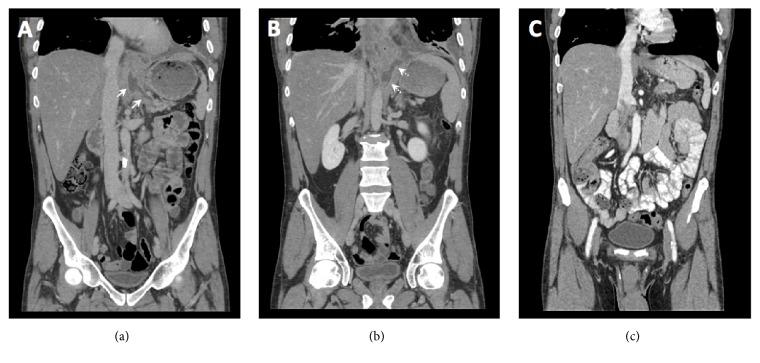

A 49-year-old male with history of chronic alcohol-induced pancreatitis presented with one month of worsening left pleuritic chest pain and shortness of breath. Chest radiograph demonstrated bilateral pleural effusions. Thoracentesis revealed increased amylase in the pleural fluid. Computed tomography (CT) and magnetic resonance cholangiopancreatography (MRCP) showed a fistula tract between the left pleural cavity and pancreas which was confirmed on endoscopic retrograde cholangiopancreatography (ERCP). Patient was treated with placement of a pancreatic stent with complete resolution of the fistula tract approximately in 9 weeks. A systematic literature search was performed on reported cases with pancreaticopleural fistula (PPF) who underwent early therapeutic endoscopy within the last 10 years. Imaging modalities, particularly CT and MRCP, play essential role in prompt preprocedural diagnosis of PPF. Early therapeutic ERCP is an effective and relatively safe treatment option for PPF, so invasive surgery may be avoided.